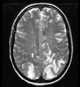

Diffuse necrotizing leukoencephalopathy

Periventricular T2 hyperintense lesion